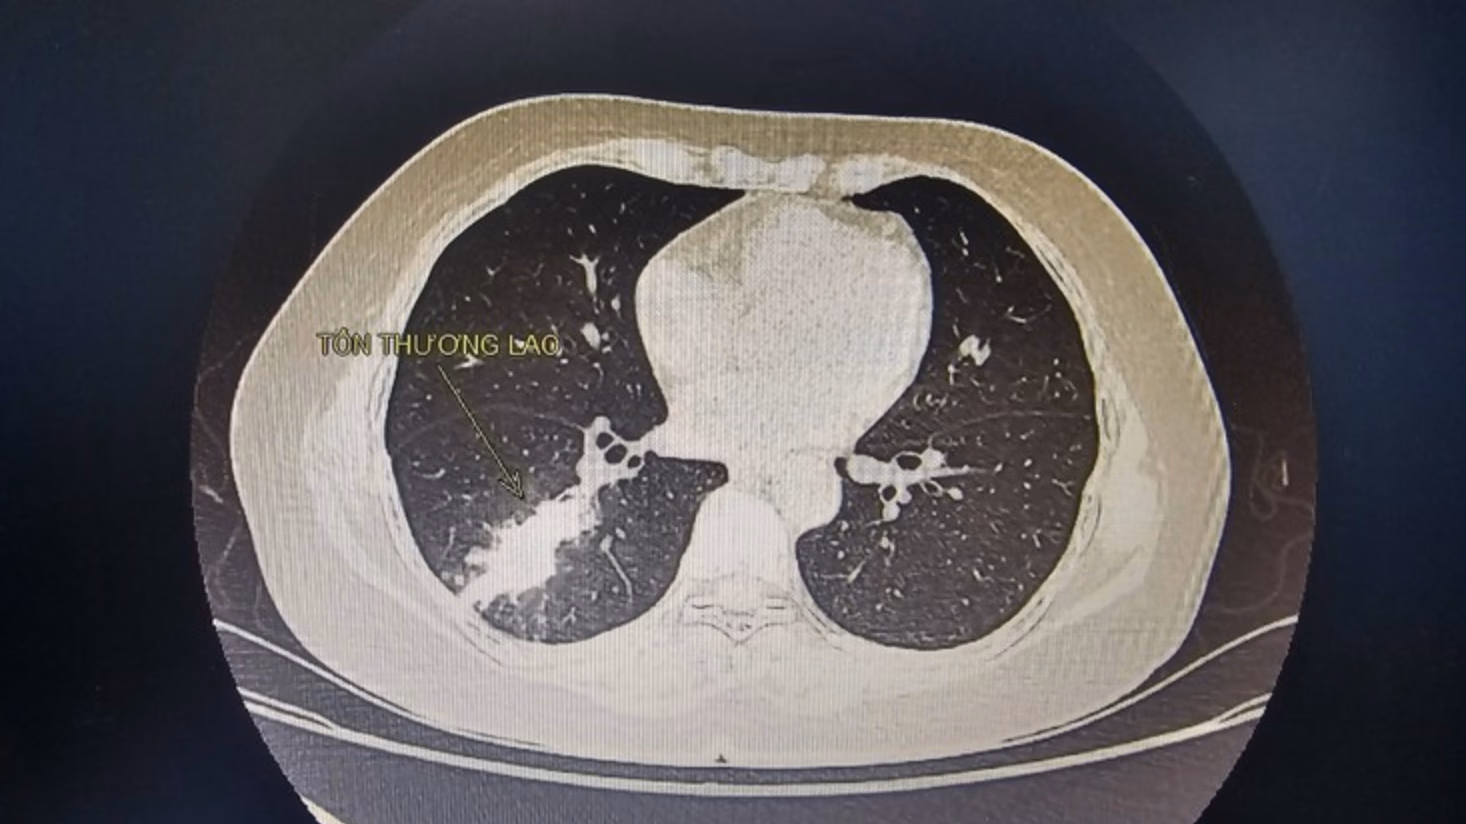

Tuy nhiên, tình trạng ho không thuyên giảm mà còn xuất hiện sốt nhẹ và ho ra máu, khiến gia đình lo lắng và đưa đi khám. Sau khi thực hiện các xét nghiệm cần thiết và chụp X-quang phổi, kết quả cho thấy bệnh nhân mắc lao phổi.